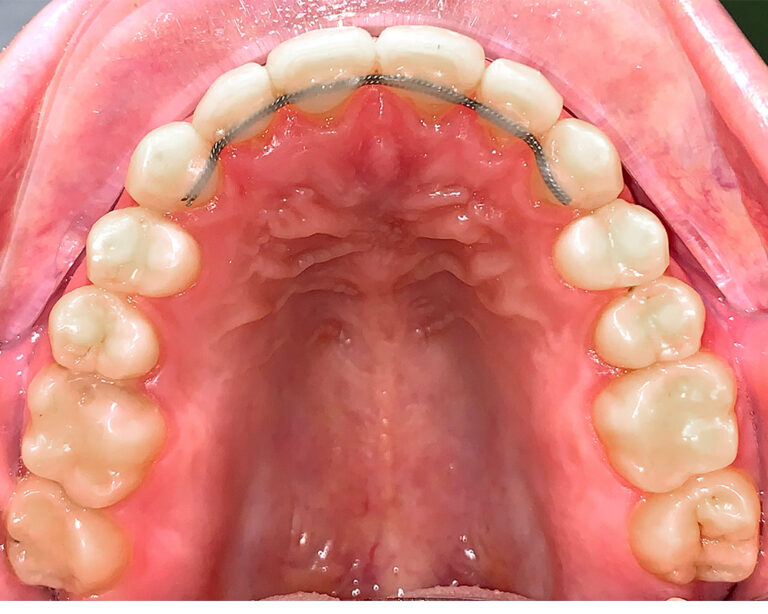

Кейс 11

Акинфиева Анна Владимировна

Количество кап ВЧ 12

Количество кап НЧ 16

ДО

ПОСЛЕ